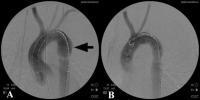

L’artériographie peut aussi être utilisée mais seulement pour explorer une région ciblée (Figure 3 et 4A).

Figure 4: Rupture de l’isthme aortique, artériographie peropératoire avant et après traitement par endoprothèse couverte